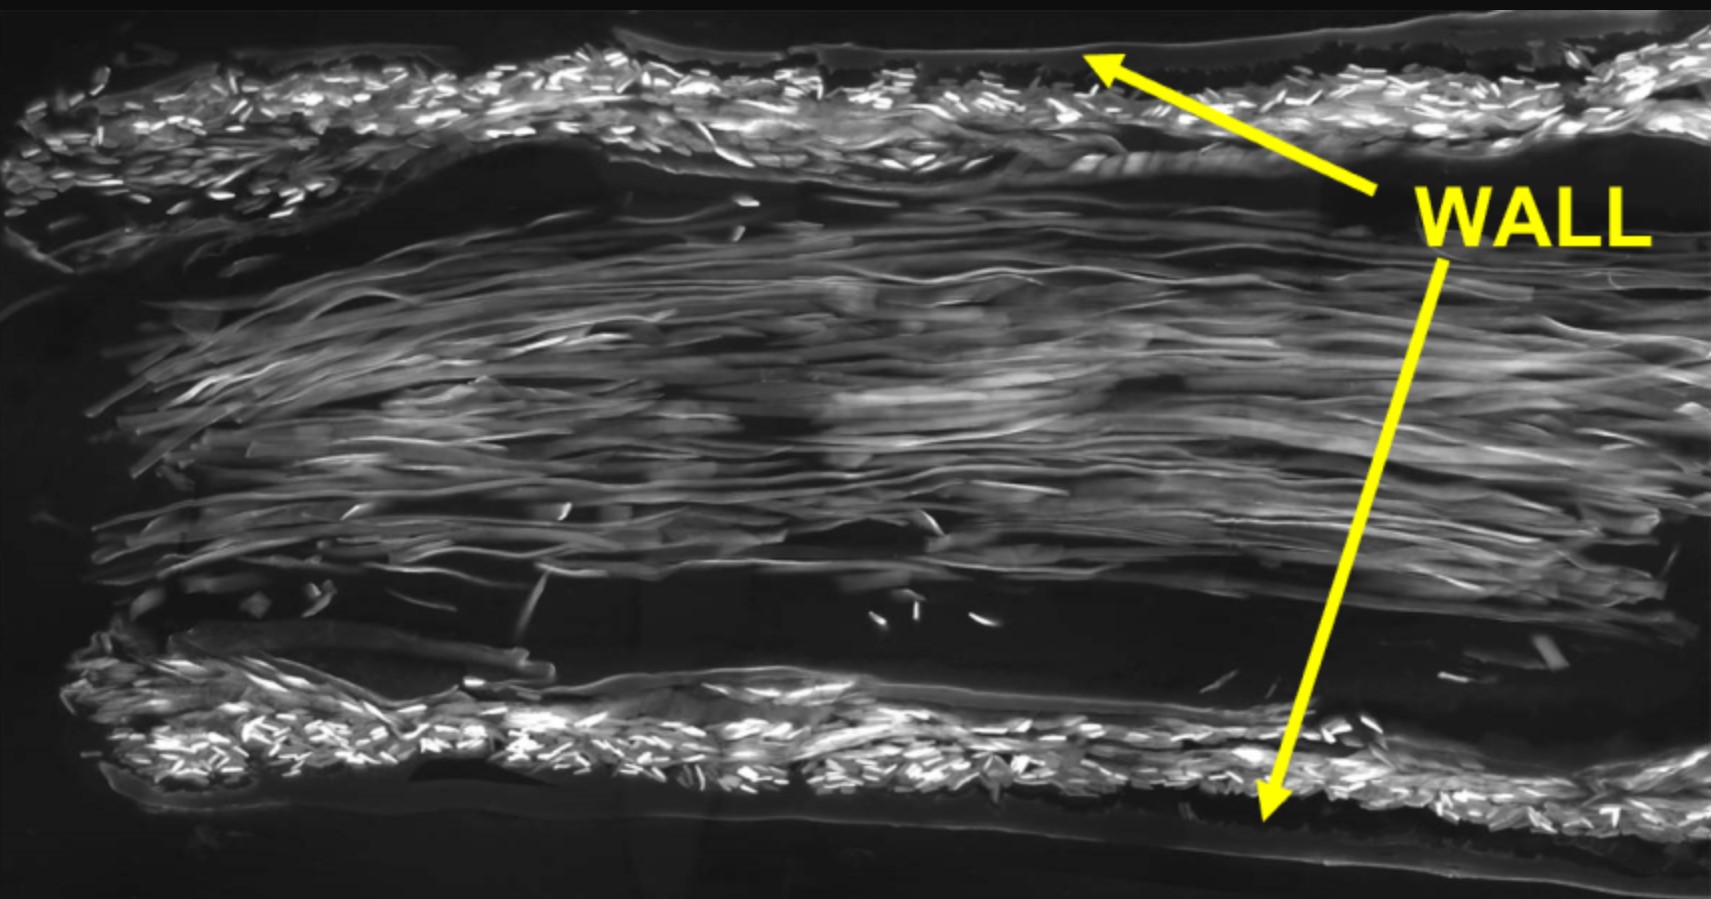

Изображение: источника. Проводники из натуральных или синтетических материалов являются важным хирургическим инструментом для восстановления поврежденных нервов. Это трубки, которые пришивают к обоим концам поврежденного нерва, чтобы направлять рост нервных волокон и клеток через разрыв. Однако в настоящее время их можно использовать только на очень маленьком расстоянии. В новом исследовании исследовательская группа разработала новый тип нервного проводника с использованием двух разных типов натурального шелка. Стенка трубки была изготовлена из шелка шелкопряда (Bombyx mori), а внутренняя часть заполнена шелковыми волокнами золотых пауков-кругопрядов (Trichonephila edulis). Трубки были протестированы на крысах, у которых был перерезан правый седалищный нерв с образованием зазора в 10 мм (значительная длина для крысы). Исследователи обнаружили, что поврежденные нервы адаптировались к новым шелковым нервным проводникам и росли вдоль шелковых нитей до тех пор, пока разорванные окончания успешно не соединились. Исследовательская группа использовала передовые методы микроскопии для детального анализа процесса заживления. Это показало, что шелковые трубки имеют очень пористую структуру; важная функция для регенерации нервов, поскольку это позволяет обмениваться питательными веществами и отходами. Статья «Silk-in-silk nerve guidance conduits enhance regeneration in a rat sciatic nerve injury model» опубликована в журнале Advanced Healthcare Materials.

Изображение: источника.